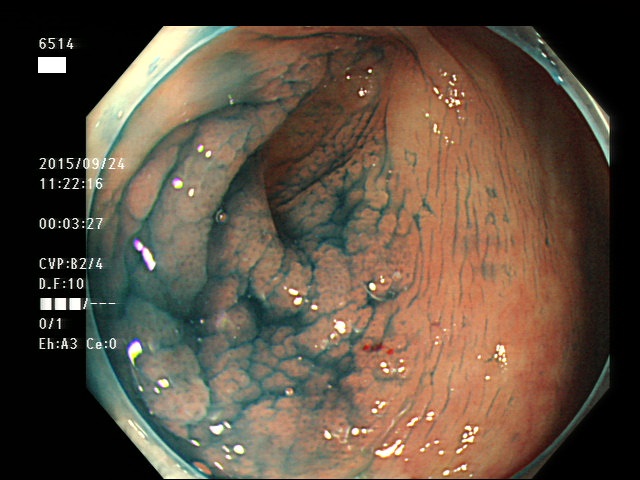

虫垂開口部の過形成ポリープ(SSAP)の例

一般に虫垂過形成ポリープが見られる方は「大腸の他の部位にもポリープ(特にSSAP)が見つかる可能性が非常に高い」のです。つまり「危険な腸である」という警告灯になるのです。虫垂は大腸の一番奥ですから「観察のスタート地点」です。ここで警告灯が出ることは非常に有益な訳です。